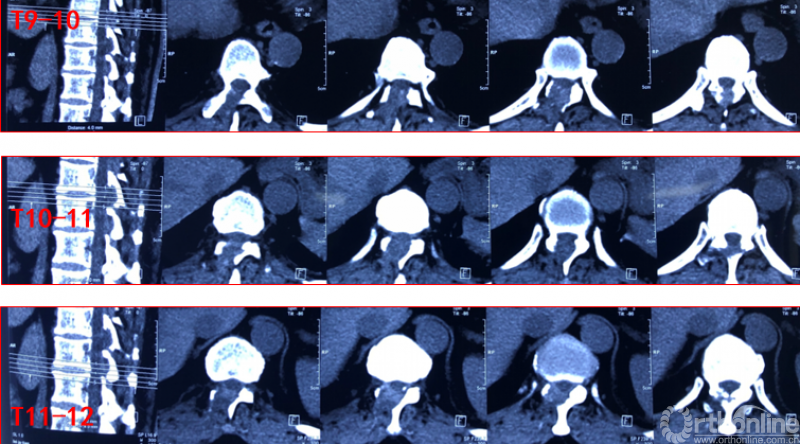

Case4:胸椎间盘突出伴韧带钙化可视化治疗

术前诊断及评分

JOA评分:5分

ASIA等级:C级

诊断:

1:胸椎间盘突出伴钙化下肢不全瘫

术前资料